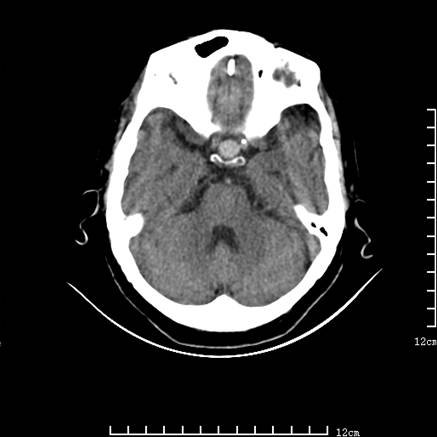

标题: V0514:女,72岁,偶有头晕,自诉记忆力减退,来诊。 [打印本页]

标题: V0514:女,72岁,偶有头晕,自诉记忆力减退,来诊。

是拉特可囊肿(rathke cyst)吗?

考虑垂体瘤可能性大

1、考虑垂体腺瘤。

2、脑萎缩ct表现。

垂体腺瘤可能性大!另:轻度脑萎缩!

考虑垂体腺瘤可能性大。脑萎缩。

考虑------垂体腺瘤可能性大----脑萎缩

考虑垂体腺瘤可能性大。脑萎缩。  建议mri 检查

垂体瘤,建议mri

垂体腺瘤